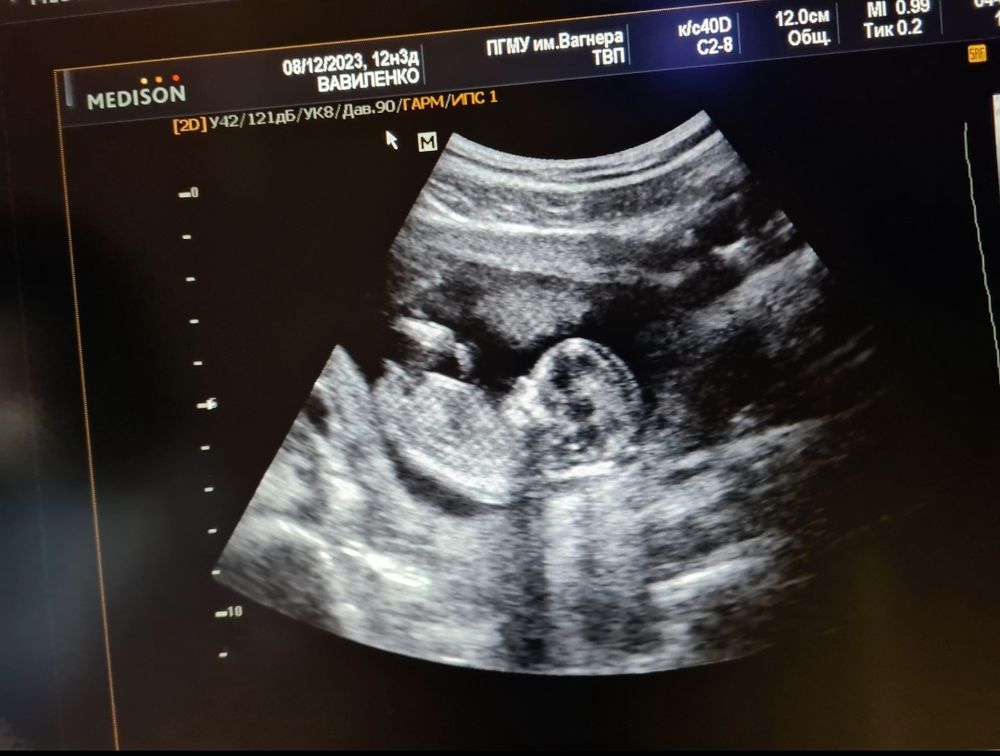

Кто по УЗИ? Тут вроде знатоки :)

у меня такой же снимок с первого скрининга, сегодня состоялся второй скрининг, подтвердили пол, девочка)) на первом скрининге предположили девочку 80% по половому бугорку

Девочка

Похоже на девочку

Лежит немного буквой зю, но ставлю на девочку)